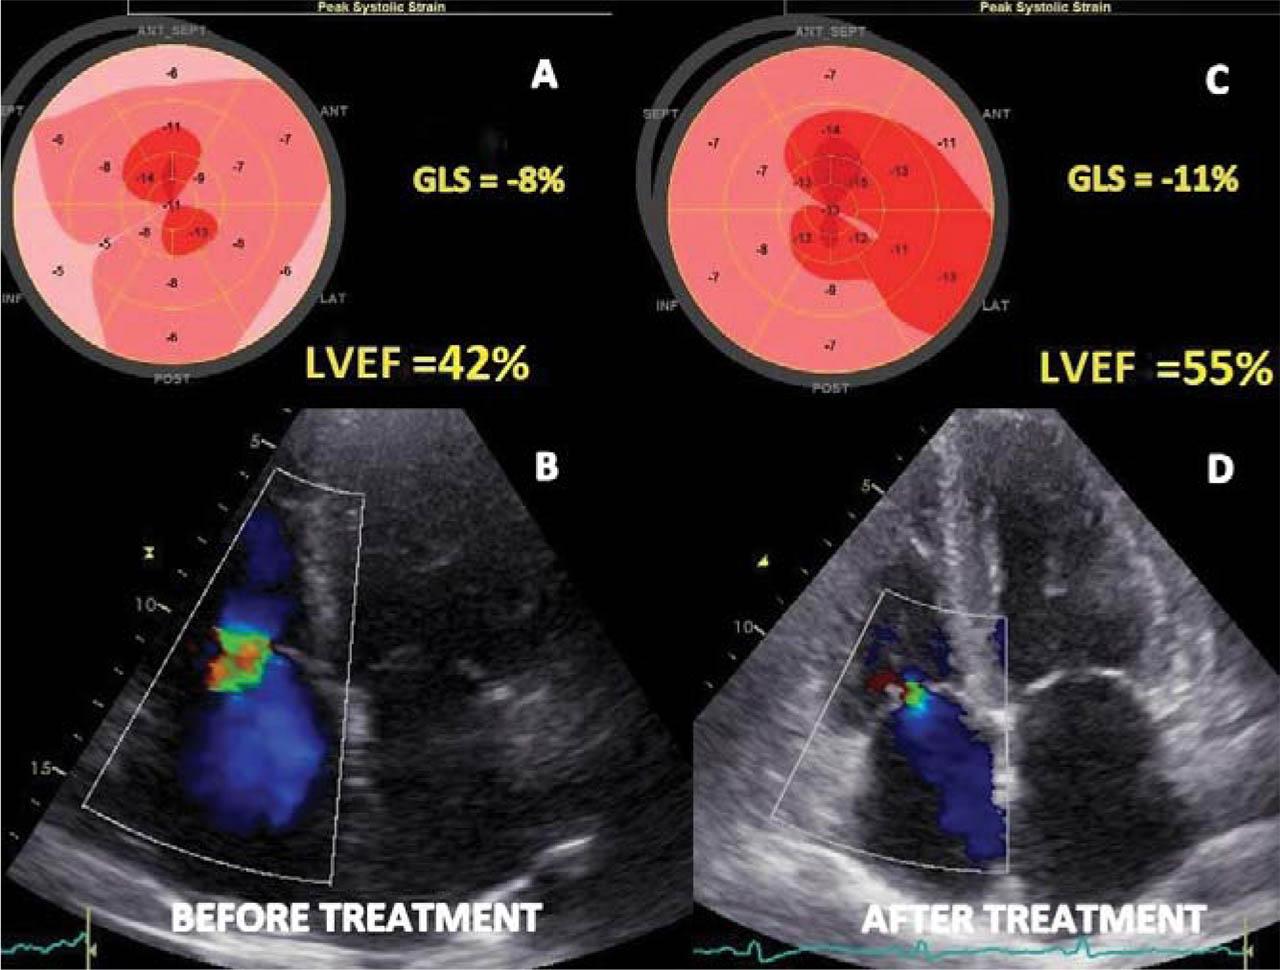

Transthoracic echocardiography (TTE) revealed nondilated LV with severe concentric hypertrophy (IVS) =17 mm, PWT =16 mm, relative wall thickness (RWT) =0.8, LV mass =157 g/m2), diffuse hypokinesia, a „ground-glass” appearance in the myocardium, and LV ejection fraction (LVEF) of 42%. A small pericardial effusion was present (Figure 2 A). Diastolic dysfunction (DD) was confirmed as grade III (E/A=3, E= 97 cm/sec, E/E’= 25) with severely biatrial dilation (LA volume = 63 ml/m2; RA volume = 54 ml/m2) and mild to moderate mitral regurgitation (Figure 2 B, C and D). The right ventricle (RV) had an increase in wall thickness (free wall = 8 mm) and severely altered systolic function (TAPSE =8 mm, S’= 5 cm/sec) (Figure 3 A and B). Severe tricuspid regurgitation with pulmonary hypertension (estimated sPAP = 46 mmHg) was also noted (Figure 4 B). 2D speckle tracking echocardiography (STE) was used to quantify myocardial deformation. Global LV longitudinal peak systolic strain (GLS) was significantly impaired (−8.4%), with a severe altered deformation in all three layers, mainly at the basal and midventricular segments and relatively preserved at the apical level, resulting in a typical apical sparing strain pattern (Figure 4A).

Figure 4

Transthoracic echocardiographic images before and after chemotherapy and stem cell transplantation. A and B (before treatment) images. A: Bull’s eye plot image showing significantly reduced GLS (−8.4 %) with severe altered deformation mainly at the basal and midventricular segments and relatively preserved at the apex, with a typical apical sparing strain pattern or „cherry-on-top” pattern. B: severe tricuspid regurgitation on Colour Doppler images. C and D (after treatment) images. C: Bull’s eye plot image showing an improvement in GLS (−11%) predominantly on the lateral and anterior wall. D: significantly regression of tricuspid regurgitation to mild by Colour Doppler images. GLS: global longitudinal strain.

The final diagnosis was AL amyloidosis (primary amyloidosis) with cardiac involvement. Cardiac specific treatment included salt restriction, small doses of diuretics (furosemide 20 mg o.d), and mineralocorticoid receptor antagonists (spironolactone 25 mg o.d) which led to a gradually improvement of congestion. We decided to continue treatment with metoprolol succinate 25 mg o.d, perindopril 2.5 mg o.d, and atorvastatin 20 mg o.d, well tolerated. Moreover, at this stage we agreed for no anticoagulation before haematological treatment. The patient was referred to a haematological centre and specific treatment with VCD (bortezomib-cyclophosphamide-dexamethasone) was started, as well as auto-stem-cell transplantation. All treatments were well tolerated, and no major side effects were observed. At 6 months follow up, the patient reported a significant improvement in her functional capacity, exercise tolerance, and presented a significantly decrease in NTproBNP level, up to 1500 pg/mL. A follow up TTE showed improvement of the LVEF from 42% to 55%, and of the GLS form −8% to −11% (Figure 4 A and C), decrease in the left and right atrial volumes (at follow up: LA = 40 ml/m2 and RA = 30 ml/m2), and a significant regression of tricuspid regurgitation, from severe to moderate (Figure 4 B and D). Moreover, there was a significant improvement in the RV systolic function (TAPSE = 15.5 mm, S’ = 9 cm/sec) (Figure 3 C and D), with a reduction in pulmonary hypertension (sPAP = 34 mmHg). All of these findings suggested a regression of myocardial inflammatory λ light chains infiltrates as a result of chemotherapy response.